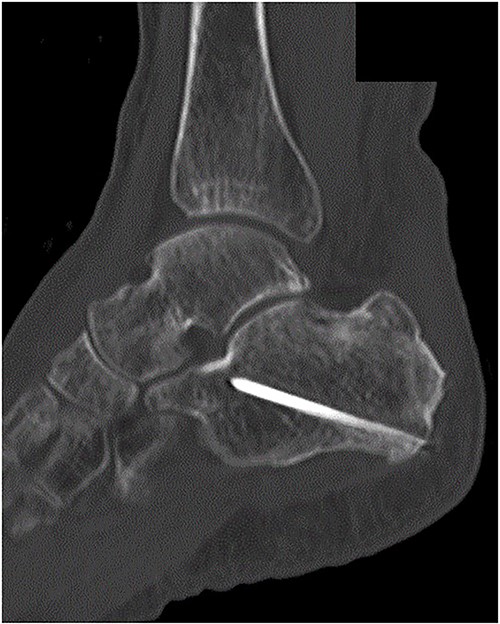

Postoperatively, a non-weightbearing short leg cast was applied for 2 weeks, and when the cast was removed, active and passive ranges of motion exercises of the ankle were started. Partial-weightbearing was allowed at 2 weeks postoperatively, and full-weightbearing at 6 weeks postoperatively. At 3 months after the surgery, non-contrast CT showed complete bone union (Fig. 4). At 2 years after the surgery, she had no symptoms and dysfunctions (Fig. 5).

At 3 months after the surgery, non-contrast CT showed complete bone union in a sagittal view.